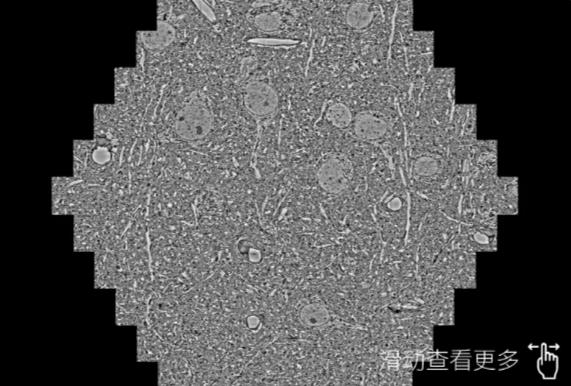

鼠脑切片。左图使用海口蔡司海口扫描电镜MultiSEM706对165μmx143pm面积区域成像,耗时仅需1.5秒。右图为鼠脑切片中30μm区域放大效果。样品由芝加哥大学B.Kasthuri提供。

使用蔡司高速海口扫描电镜MultiSEM对1mm²人脑皮层组织进行高分辨成像,并对其中的各种细胞结构进行三维重构分析。左图展示了2x3mm²组织平面中锥体神经元的三维重构效果。右图显示了局部体积神经元三维重构。图像由哈佛大学chtman实验室提供,渲染图由D. Berger 制作。